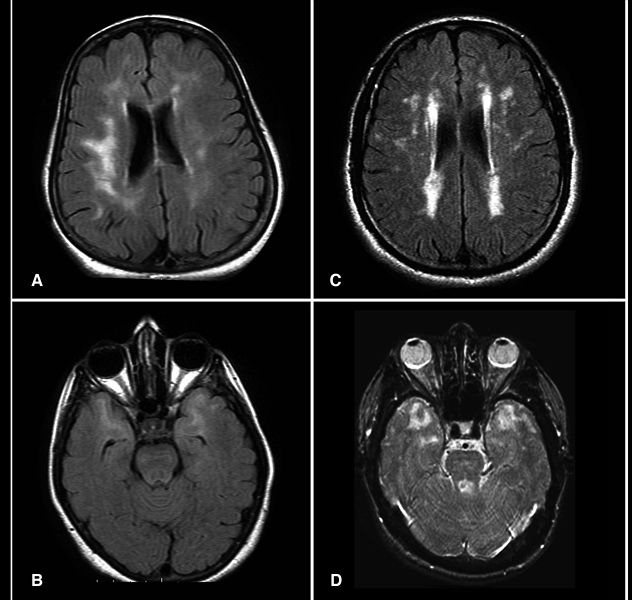

MRI’da insan veya diğer memeli beyinlerinde görüntülenen yüksek yoğunluktaki alanlardır.

MRI’da insan veya diğer memeli beyinlerinde görüntülenen yüksek yoğunluktaki alanlardır.